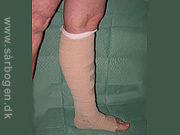

Kompressionbandage

Zoom

Zinklimbind